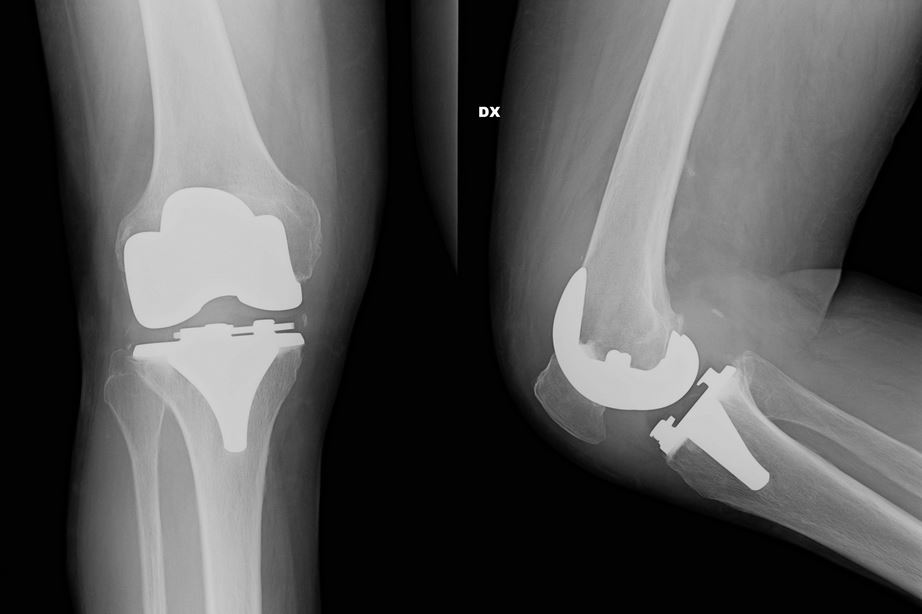

La novità consiste nella personalizzazione della protesi: prima di operare, infatti, viene fatta una TAC (acronimo di tomografia assiale computerizzata) che studia l’osso, permettendo all’ingegnere e al chirurgo di adoperare una serie di scelte esclusive per quel ginocchio e per quel paziente. La protesi, che viene installata in un’ora, è quindi un abito su misura, e consente un recupero totale del ginocchio. Questo protocollo nasce in Svizzera e si è diffuso soprattutto in Francia e Spagna, ma poco in Italia. Attualmente sono solo quattro i centri a cui ci si può rivolgere: a Genova, a Roma, ad Arezzo e a Bologna. Gli interventi di protesi di ginocchio nel 2014 sono stati circa 85mila in Italia e sono sicuramente in aumento.

“La qualità dei risultati – precisa il Mario Manili ortopedico, Socio SIOT – Società di Ortopedia e Traumatologia- Consulente presso il Centro Chirurgico Toscano di Arezzo e la Clinica Villa del Rosario di Roma – dipende dalla precisione dell’applicazione della protesi, perché bisogna togliere la parte malata, riequilibrare l’asse del ginocchio, intervenendo quindi anche sui legamenti, e fissarla all’osso. Tutto questo si fa con un gesto unico, ma richiede un altissimo livello di precisione, altrimenti si rischia un risultato poco efficace. C’è soltanto un 2% dei pazienti che continua a subire un lievissimo dolore, ma di gran lunga inferiore al precedente. Con il tempo però, anche in questi casi, si raggiunge il perfetto equilibrio”.